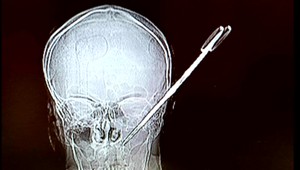

Žena zapichla mužovi nožnice do hlavy, ten zázrakom prežil

Krimi